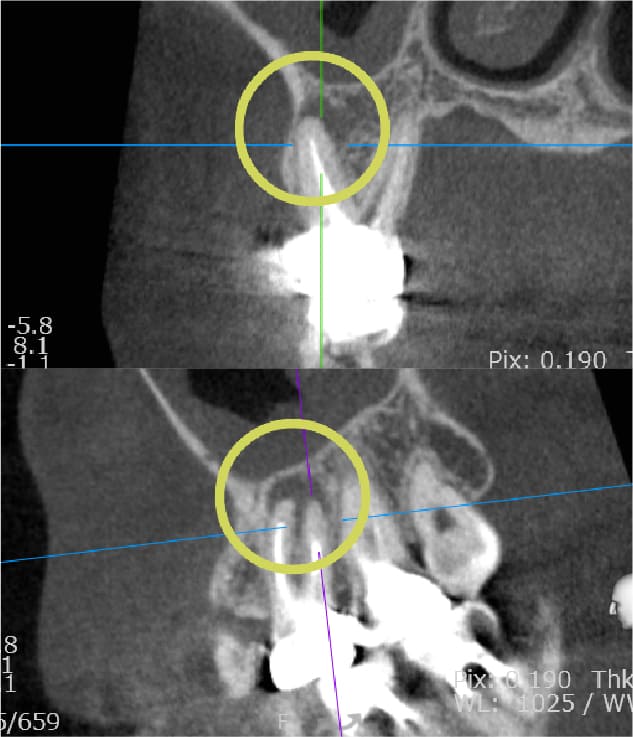

| 歯科用CTによる三次元診断 | 拡大ルーペの使用 |

| 一般的なレントゲン(二次元)では見えない、歯根の複雑な構造や病巣の位置を立体的に正確に把握し、治療の見落としを防ぎます。 | 肉眼では困難な根管内の細部を約8倍に拡大して確認し、処置の精度を高めます。 |

| 歯科用CTによる三次元診断 |

| 一般的なレントゲン(二次元)では見えない、歯根の複雑な構造や病巣の位置を立体的に正確に把握し、治療の見落としを防ぎます。 |